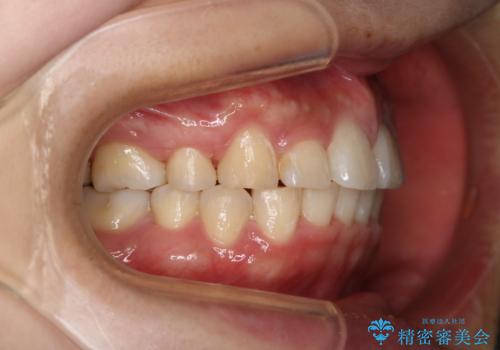

- 前歯のがたつきが気になるとご相談にいらした方です。当初は前歯の部分矯正をご希望されていましたが、全体的に整えることで審美的、機能的な歯並びとなりました。

当初は上顎前歯のみの部分矯正をご希望されていましたが、部分的に前歯のみを並べると出っ歯感がつよくなり、食事もしづらくなる可能性をお伝えしました。全顎的な矯正治療により、審美的、機能的な歯並びとなりました。